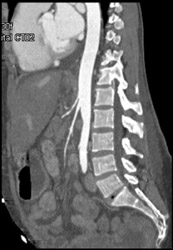

Left Renal Artery Stenosis With Decreased Renal Size